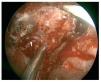

Caso clínico: Varón de 42 años de edad con paresia del VI par craneal derecho y estudios de imagen mediante resonancia magnética y tomografía computarizada craneales sugestivos de displasia fibrosa esfenoclival. Se lleva a cabo un abordaje endonasal expandido transpterigoideo completamente endoscópico, obteniéndose una amplia descompresión de las estructuras vasculonerviosas de la base del cráneo. Durante el procedimiento se utiliza neuronavegación y el canal vidiano como referencia anatómica fundamental de la carótida en su segmento lacerum.

Case report: A 42-year-old male with right sixth cranial nerve palsy. Cranial MRI and CT showed a central skull base lesion with diagnostic suspicion of FD. Patient underwent a full endoscopic transpterygoid EEA, achieving a wide skull base neurovascular decompression. Neuronavigation and the vidian canal landmark resulted mandatory during intraoperative procedure.